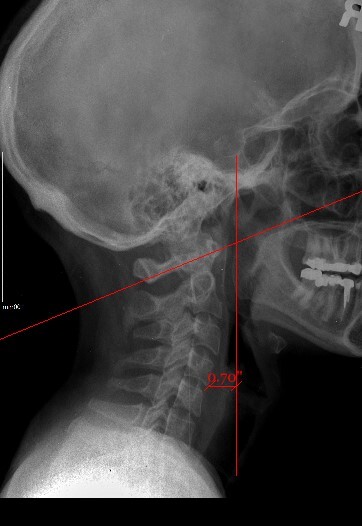

Upper cervical orthogonal based x-rays to measure for significant upper cervical misalignment.17,21,22 (Figure 2 a,b,c)

These films are used to determine atlas misalignment, develop a correction strategy and confirm an appropriate correction has been made.